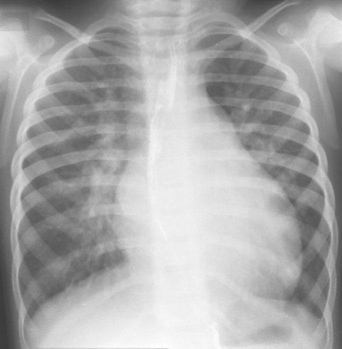

Se pueden encontrar los siguientes hallazgos:

- Edema septal (líneas de Kerley).

- Edema perivascular y peribronquial con pérdida de definición y borrosidad de los vasos y bronquios de mediano calibre.

- Edema subpleural (visión de las cisuras interlobares).

- Edema alveolar en “alas de mariposa”.

- Cardiomegalia.